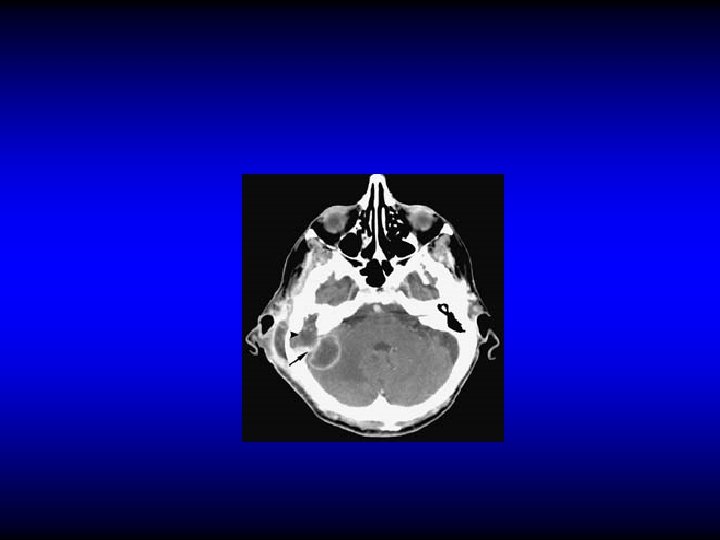

Petrositis (petrous apicitis) An extension of infection from the middle ear pneumatized petrous apex. into a

Diagnosis of petrositis • Gradenigo’s syndrome – Otitis media (otorrhea) – Retro-orbital pain – Squint (VI cranial nerve palsy) • Imaging

Treatment of petrositis • Antibiotics and myringotomy • Surgical drainage if medical treatment fails